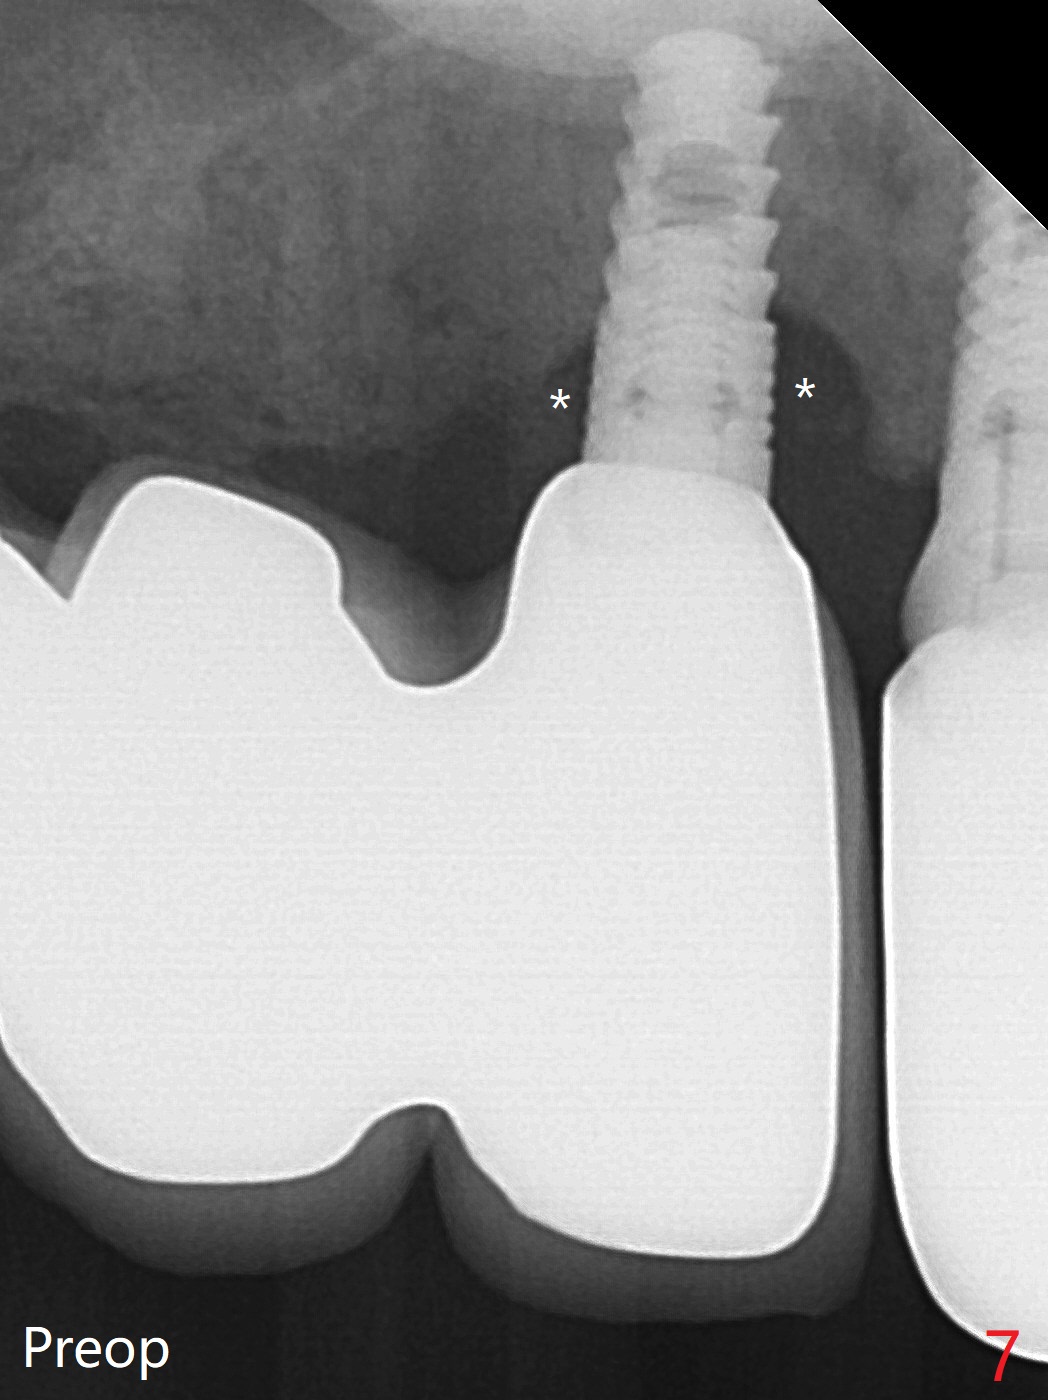

64岁女3-7牙桥,7号牙植体颊侧牙龈缘红肿(图一:*),脓液(图二:^),需要切开清洗,但是6号牙桥墩颊侧非角化龈(N)妨碍切口,所以必须去除桥墩,暴露牙槽嵴顶角化龈(图三:K),容易切开,最后缝合而不容易出血,伤口容易愈合。切开清创后重大发现是牙冠边缘(图四:^)直接接触植体微螺纹,没有基台与牙龈之间形成的屏障,有利于口腔细菌直接感染植体。直感告诉术者必须缩短牙冠边缘,抛光。然后缺损处放置粘性骨粉(图五,八:S,与图七(术前)比较),表面覆盖PRF膜,缝合(图六)。准备术后尽早去除牙冠,预防细菌再次感染。并且在6号牙位植入2x8.5毫米植体。